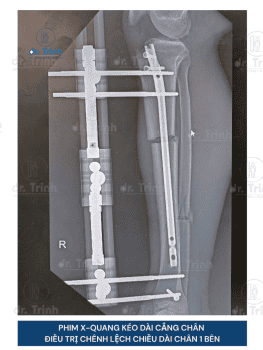

Phẫu thuật kéo dài chân là phương pháp phẫu thuật giúp cải thiện chiều cao giúp cho những người muốn cải thiện chiều cao và vóc dáng. Trong nhiều trường hợp, phẫu thuật kéo dài chân còn giúp điều chỉnh các bất cân xứng chi (chân lệch, chân ngắn bẩm sinh, chênh lệch chiều dài chân sau chấn thương), có thể góp phần mang lại sự cân đối và chức năng vận động tốt hơn.

- Phương pháp phẫu thuật: Đinh nội tủy tự động Precice, khung tròn, khung thẳng mới..

- Vị trí kéo dài: Kéo dài xương đùi hoặc xương cẳng chân có chi phí khác nhau

- Số chân cần phẫu thuật: 1 hoặc 2 chân